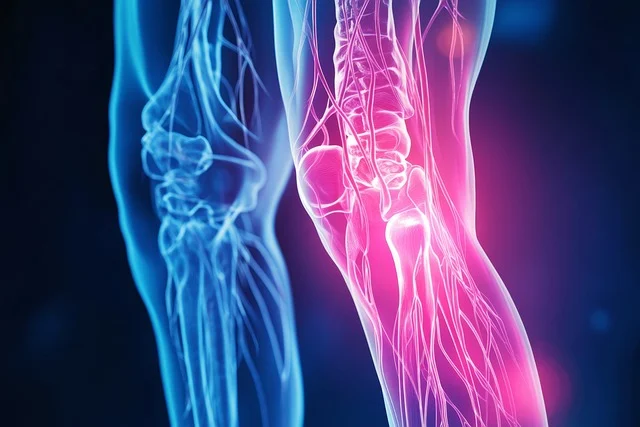

무릎통증 원인

무릎통증 증상